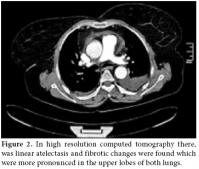

In high resolution computed tomography (HRCT) there was linear atelectasis, and fibrotic changes were found which were more pronounced in the upper lobes of both lungs (figure 2). Mild to severe pericardial effusion was seen in echocardiography (ECHO; figure 3). Three days after 20 mg intravenous prednisolone therapy, fluid accumulation was considered to be gradually decreasing in ECHO (figure 4).